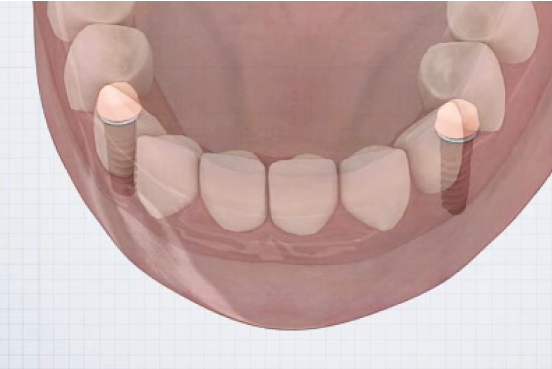

Direct Technique

①

- Healing Abutment 제거- Plastic Carrier을 이용하여 EZ LOCK Abutment 체결

Indirect Technique

①

- 잇몸 높이에 맞는 EZ LOCK Abutment 체결▼